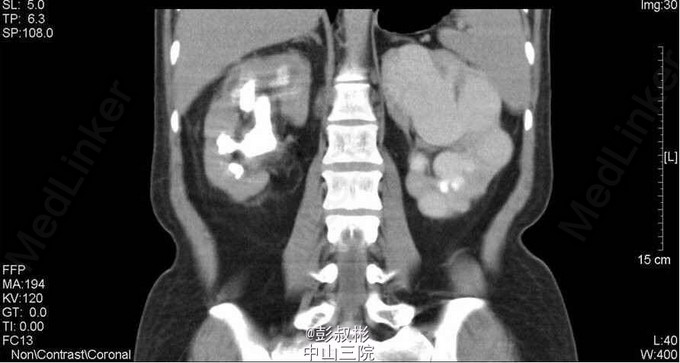

1、因“反复下腰部胀痛伴发热2月,加重10天” 入院。入院前最高体温39.5℃ ,外院检查尿隐血及尿白细胞3+,进一步行泌尿系B超显示双肾及左输尿管下段结石,左肾重度积液 。 2、既往史: 10年前因肾结石行体外冲击波碎石术,自诉术后恢复良好。 3、辅助检查:1) 血常规(抗炎后)、血生化(补钾后)、肝功、凝血、术前八项、胸片及心电图未见明显异常; 2) 尿常规:12.9 :尿液白细胞+++ 尿液红细胞++ 左肾造瘘液白细胞++ 左肾造瘘液红细胞++ 3) 真菌培养:无真菌生长 4) 肾功能:12.9: 肌酐5.68 mmol/L尿素氮: 186 nmol/L 5) 核素肾动态显像+GFR双血浆测定 1.右肾灌注、功能中度受损,右上尿路慢性梗阻。 2.左肾灌注、功能中度受损,左上尿路机械性梗阻。 灌注相:双肾于腹主动脉显影后2秒开始显影,放射性灌注明显减低(右肾明显低于左肾)。灌注曲线分析:双肾灌注峰明显减低。 功能相:右肾影稍增大,放射性摄取明显减低,放射性分布不均匀,可见多发放射性分布稀疏缺损区,放射性排泄缓慢。左肾增大,放射性摄取减低,放射性分布不均匀,可见多发放射性分布稀疏缺损区,放射性排泄缓慢,左肾盏见明显放射性滞留。半小时内膀胱可见放射性积聚。 肾图:右肾a段降低,b、c段融合为低水平延长型肾图。左肾a段降低,b、c段融合为持续上升型肾图。双血浆法肾小球滤过率(GFR)左肾为19.7ml/min,右肾GFR为17.9ml/min。 6) 双肾CTU平扫+增强螺旋扫描 1、左肾多发结石、重度积液、肾功能减退,左输尿管膀胱入口处结石,左侧输尿管炎症; 2、右肾多发结石、轻度积液,右肾功能减退,右肾盂及输尿管炎症。 4、诊断:双肾积脓 右肾铸形结石 左肾多发结石 左输尿管下段结石碎石术后 双肾功能减退 5、入院后处理:予以“舒普深” 3.0 Bid 抗感染,12-5 行“B超引导下经皮左肾穿刺造瘘术”,每日引流出约1500ml脓液。肾功能改善后于12-9行“左侧输尿管镜下钬激光碎石取石术”,术程顺利,术后予以舒普深3.0 Bid抗感染,体温正常。昨日下午行“B超引导下经皮右肾穿刺造瘘术”。